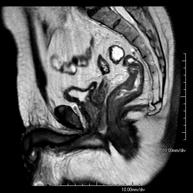

- Female pelvis MRI

This non-invasive diagnostic procedure uses an electromagnetic field and radio waves (from a transmitter and receiver) to acquire high-definition anatomical images of the pelvis. It is a radiation-free procedure. It is performed to study pathologies of the uterus, ovaries, fallopian tubes and vagina, whether they are of tumour, inflammatory or vascular origin. The procedure also enables the assessment of adjacent structures located in the pelvis, identifying any abnormalities. Sometimes intravenous contrast (gadolinium) is required to characterise the lesions.

- Male pelvis MRI

This non-invasive diagnostic procedure uses an electromagnetic field and radio waves (from a transmitter and receiver) to acquire high-definition anatomical images of the male pelvis. It is a radiation-free procedure. No prior preparation is required. In some cases, paramagnetic contrast (gadolinium) is required to characterise the lesions. This test enables the assessment of organs such as the urinary bladder, the junction between the ureters and the bladder, the prostate, the seminal vesicles, the urethra, the pelvic bones, etc.